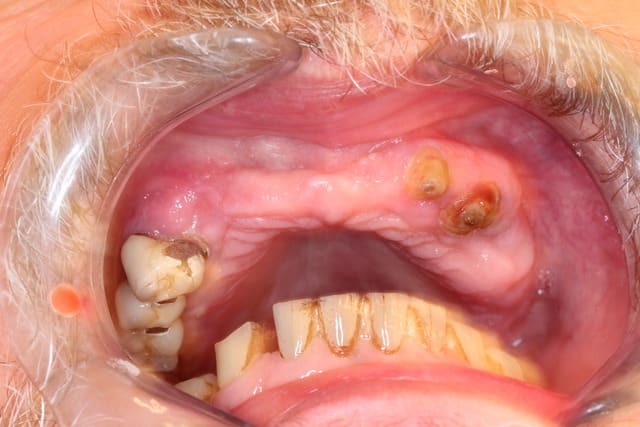

Programmé le 24 sept pour vous faire patienter mieux

Maxillaire complet extraction - implantation

Pas possible de poser que des cylindres voire même très peu voire aucun

Regardez bien les ostéolyses autour des canines